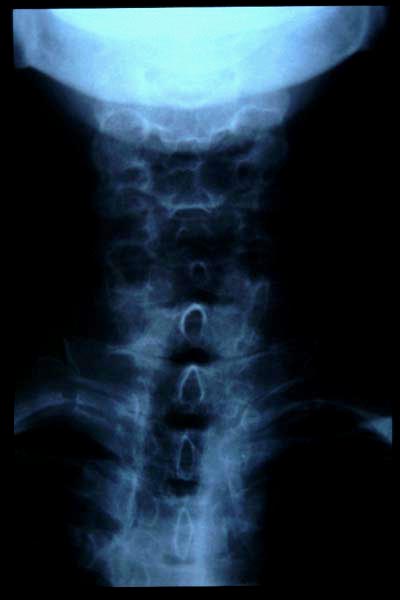

Artrosis cervical.